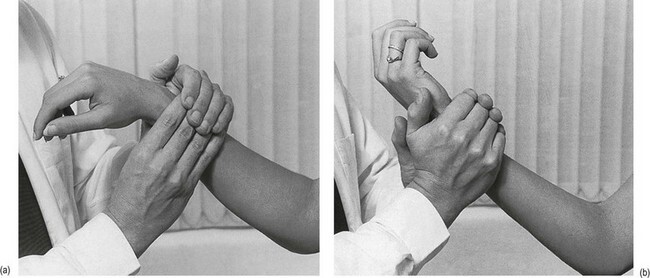

4) 손목관절조영

- 조영제를 사용하여 관절강내 조영을 하고 추가적으로 약물까지 함께 투여할 수 있습니다.